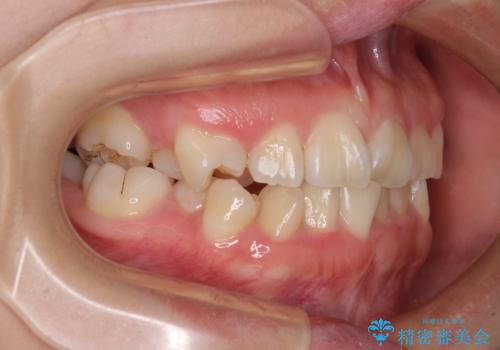

- 内側に生えている歯や埋もれた奥歯を気にして来院された患者様です。

顎の骨が小さいため、歯列が収まりきらずに叢生や未萌出となっている状態でした。

埋もれた奥歯を萌出させ、さらにデコボコを解消するために、上下左右の第1小臼歯4本に加え、親知らず4本も抜歯し、ワイヤー装置にて矯正治療を行うこととしました。